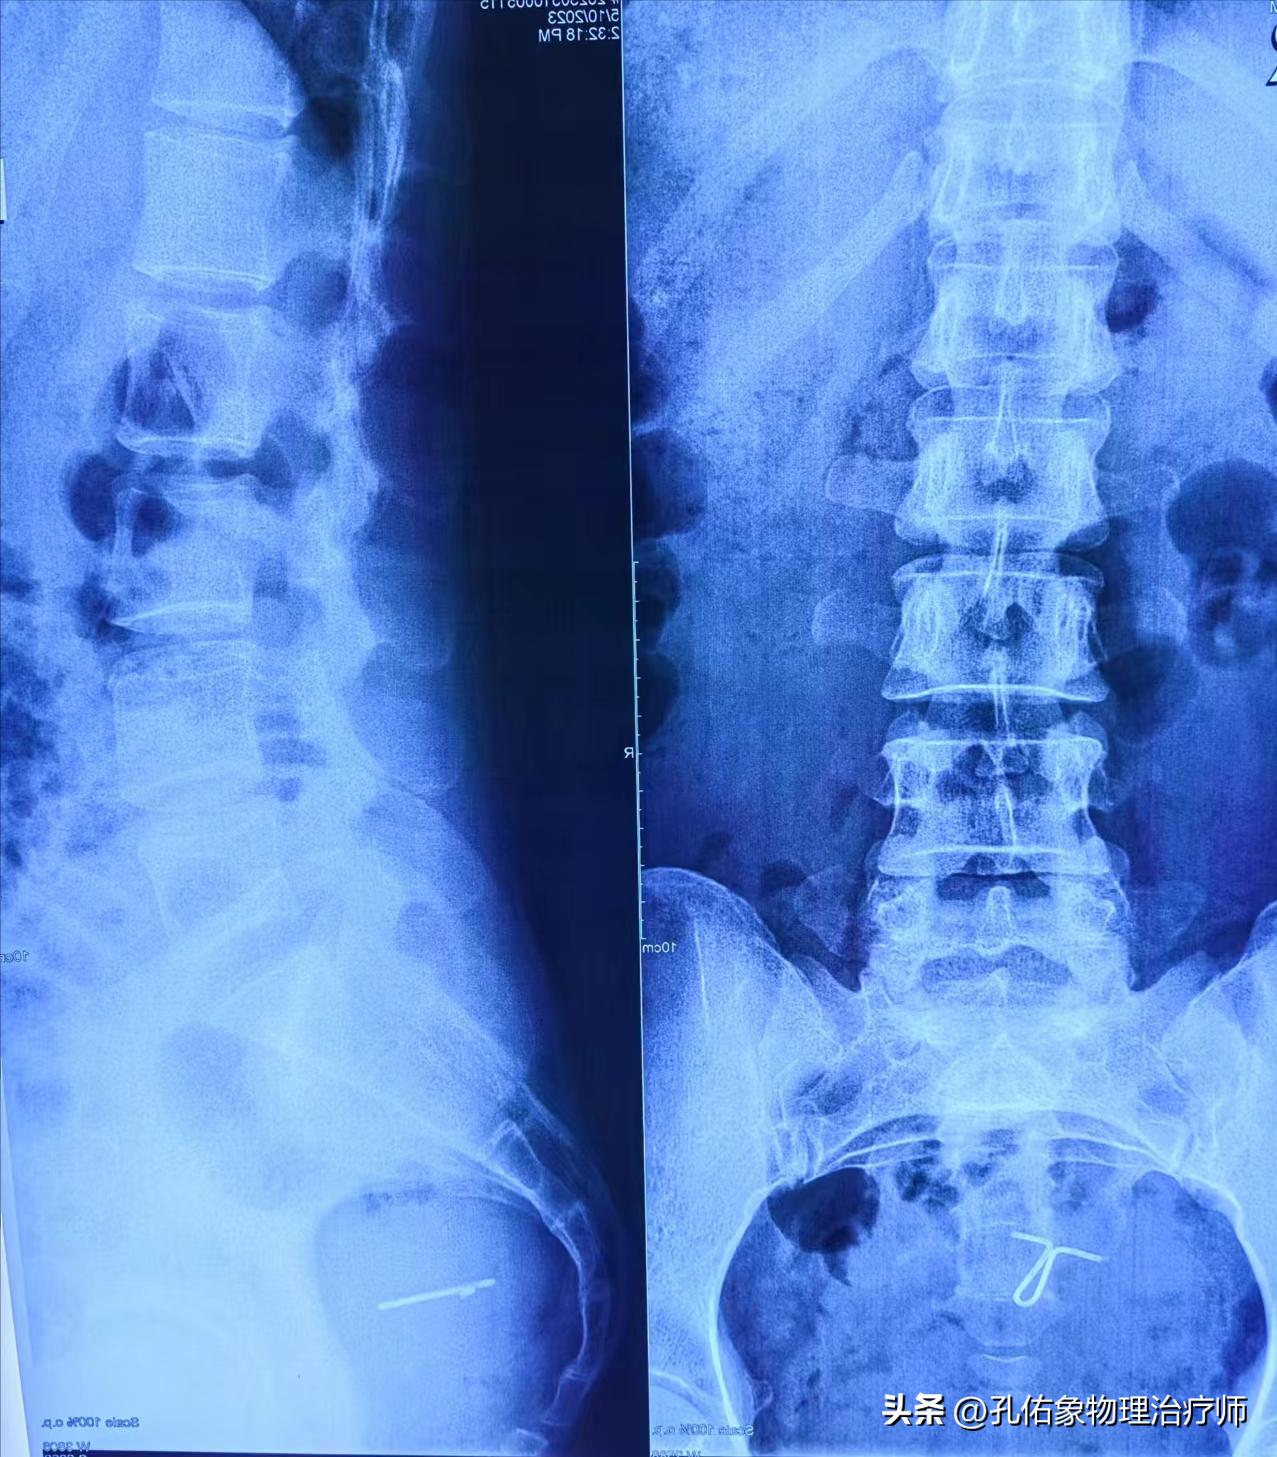

让其拍摄腰部X片,如下图所示:

阅片得知,腰5椎体相对骶1椎体移位,并有旋转;同时腰3/4/5椎也有不同程度的旋移,左右骨盆不对称。